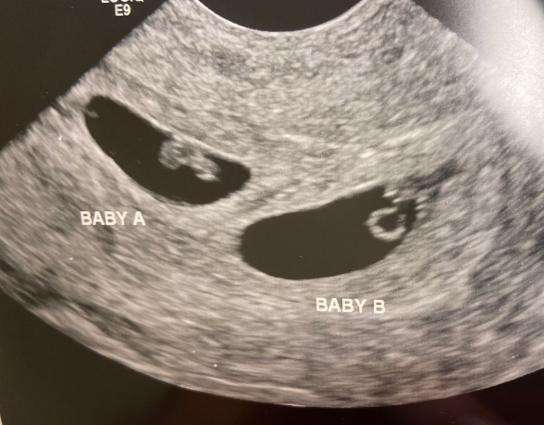

Después de estar congelados durante 30 años, tres embriones fueron implantados con éxito en una mujer estadounidense. Quien dio a luz a mellizos, el pasado 31 de octubre de 2022. […]